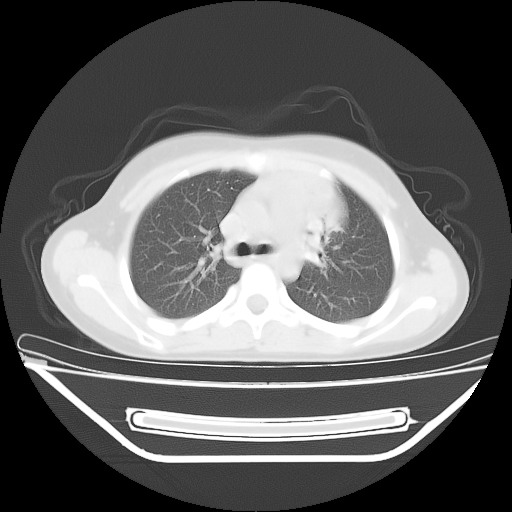

经过胸部穿刺活检为支原体感染。以下示抗支原体感染30天后所见,病灶明显缩小,临床症状消失: